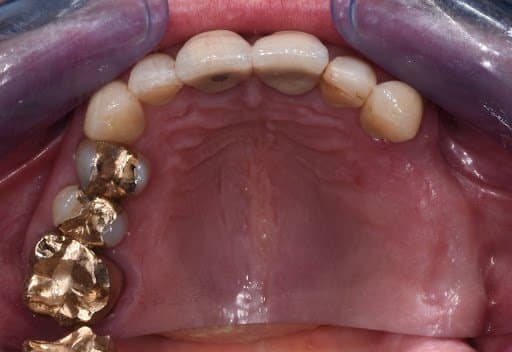

Occlusal view of initial clinical situation